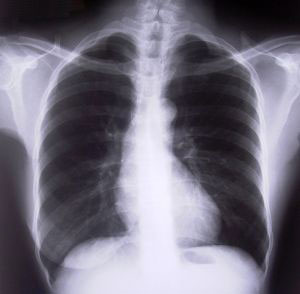

마르고 키가 큰 체형의 젊은 연령층이 격한 운동 중에 갑작스러운 가슴통증과 호흡 곤란 증상이 생기면 기흉이라고 의심해 볼 수 있다. 기흉의 진단은 매우 간단하다. 의사의 간단한 문진과 청진 후 흉부사진 촬영을 통해서 진단할 수 있다.

기흉의 치료는 먼저 흉강 내에 찬 공기를 제거하는 것이다. 일반적으로 흉강에 찬 공기 양이 적으면 적절한 환경에서 안정을 취하기만 해도 상태가 호전된다. 흉부 X레이 사진상 기흉의 양이 20%이상이고 단기간내에 치료가 필요한 경우, 손가락 굵기의 관을 갈비뼈와 갈비뼈 사이에 관을 삽입하는 흉관삽관술을 통해 공기를 제거하게 된다.